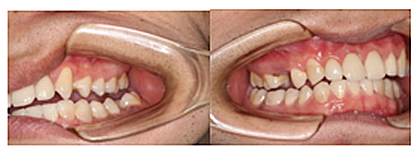

治療是從5月份開始的,醫(yī)生給我的主人驗了血,做手術(shù)前的準(zhǔn)備,還給我們都用超聲波好好的都洗了個澡,把之前依附在我們身上的牙結(jié)石都沖了個干凈(齦上潔治術(shù))。治療先從我和其他3個兄弟開始。在麻藥的作用下,我們兄弟4個都被打開了身體,去除了已經(jīng)被蛀牙破壞的牙體,做了根管治療。

因為對我們的治療需要分多次進行,因此初次治療后做了臨時牙

第二次治療是半個月后,這次做了根管充填后將覆蓋在我們身體上的一部分牙齦切除,讓我們埋于牙齦下的身體暴露了一部分,也就是醫(yī)生說的冠延長術(shù)。這是為了讓我們變得美觀一些。